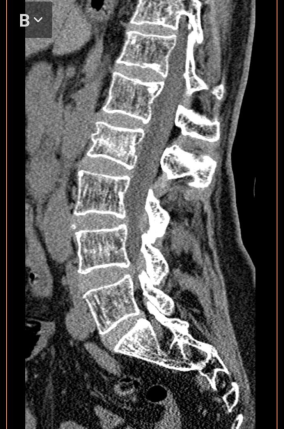

Еще двум пациентам выполнена стабилизация транспедикулярными системами с выравниванием деформации позвонка. Остальным пациентам проводили лечение блокадами и применением корсета. Из числа консервативно пролеченных больных выявлены около 4 случаев остеопороза. Переломы в этих случаях захватывали тела позвонков с 1 степенью перелома (рис. 3). В дальнейшем этим пациентам была выполнена пункционная вертебропластика.

Рис. 3. Компрессионный перелом L2 позвонка с болевым синдромом. Компрессия 1 степени без изменения кифотического угла

При консервативном лечении переломов с остеопорозом позвоночника болевой синдром сохранялся в той или иной степени. Это свидетельствовало о том, что деформация позвонка либо продолжается, либо суставно-связочный аппарат перенапрягается.